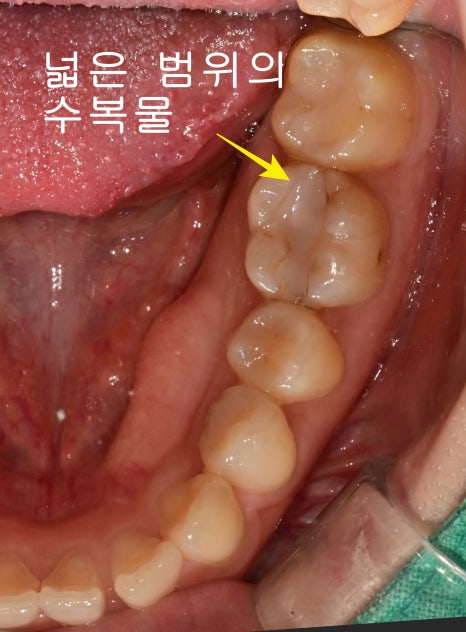

과거 치료한 넓은 범위의 수복물

구강 내 사진에서도 과거에 치료했던 금으로 된 인레이 주변으로

크랙 라인이 관찰되고 있습니다.

오래된 금으로 만들어진 인레이 치료가 된 치아에서 종종

치아의 크랙을 발견하는 경우가 있습니다.

해당 치아는 과거의 넓은 범위의 수복물이 있지만 상태는 불량해 보였고

첫날 근관치료가 마무리될 때 사진입니다.

좌우를 가로지르는 크랙라인이 관찰됩니다.